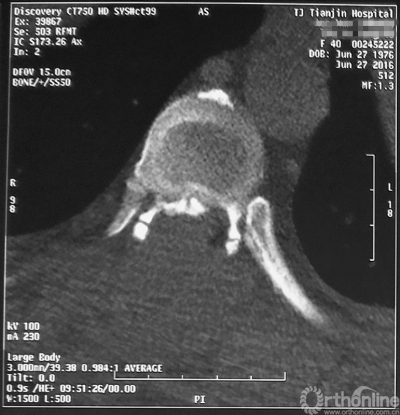

最终,由任万陆主任亲自为患者进行了全身麻醉,苗军主任为其实施了后路的胸8-10椎板减压术,手术麻醉过程平稳,手术出血不多,术后不仅没有截瘫,神经功能进一步恢复,好转出院。术后一个月随访,患者已经可以扶助行器行走,患者对疗效非常满意。

术后CT